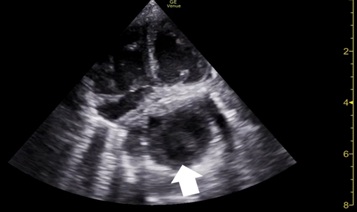

However, on day seven, frequent episodes of tachypnoea and desaturation after meals and a 20-mmHg systolic differential between upper and lower limbs were noticed, with poor perfusion. Echocardiogram demonstrated a dynamic left atrium, which was being compressed by the stomach (figures 6 and 7), with repeat diaphragmatic and abdominal ultrasound (figure 8) and thoracoabdominal contrast radiography (figure 9) showing recurrence of the hiatal hernia, prompting cessation of enteral feeds.

Figure 6: Echocardiogram on day 7, after a meal, showing left atria compression by the stomach (arrow).

Figure 7: Echocardiogram also on day 7, but now on food break, showing resolution of the left atria compression.

The newborn's hiatal hernia was diagnosed in the third trimester of pregnancy and was the first manifestation of his systemic disease. Bedside echocardiography, diaphragmatic, and abdominal ultrasounds during the first week of life showed intermittent hiatal hernia with intermittent compression of the left atrium. The increased gastric size after meals and consequent worsening of the stomach's protrusion to the chest cavity may be responsible for the desaturation, probably related to severe gastro-oesophageal reflux and subsequent aspiration. The blood pressure differential noticed between the upper and lower limbs was probably a consequence of the stomach's compression of the left atrium.